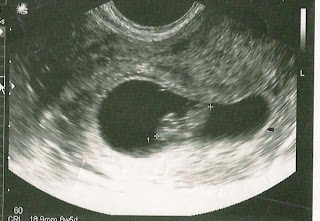

Every day is a walk on eggshells waiting for the inevitable. I can say the only saving grace we have is the advent of modern medicine. At 6 weeks, we got an ultrasound. And saw the little heart beating it's rapid beat right away.

![]() |

| 6 weeks 4 days. |

Now, we've lost one after seeing that heartbeat so while we felt some encouragement, we were still very hesitant to let it mean anything.

Then, we got another ultrasound at 8 weeks. And that little flicker of life lit the flame of hope in our hearts.